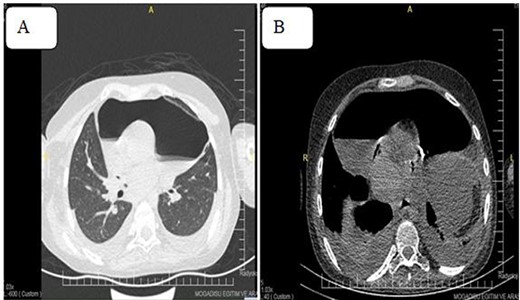

Despite therapeutic Pericardiocentesis, the patient’s clinical has not resolved. Therefore, computed tomography (CT) of the chest was requested, which revealed a thickened pericardium with pneumopericardium, as shown in Fig. 4.

Pneumoprecadium on chest CT (A) and moderate pleural effusion (B).